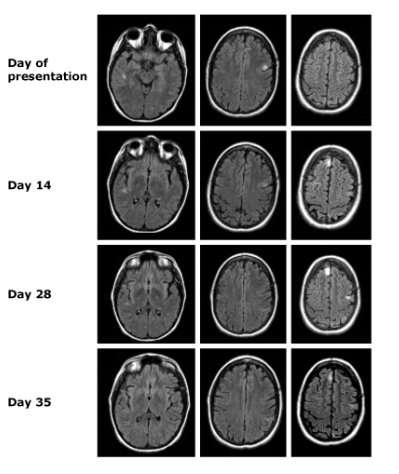

Figura 1. T2 Hiperintensidad en el Hipocampo Derecho

"¿Huellas de una convulsión? 🧠✨ Esta RM muestra hiperintensidad en T2 y restricción de difusión en el hipocampo derecho y el tálamo ipsilateral. Aunque estas señales son típicas de una actividad convulsiva reciente, la diferenciación con encefalitis herpética es clave, dado el patrón limitado al hipocampo. Un caso que nos reta a mirar más allá de lo evidente."Fuente: Gaillard F. Seizure related restricted diffusion. Case study. Radiopaedia.org. Consultado el 28 de enero de 2025. https://doi.org/10.53347/rID-46058.